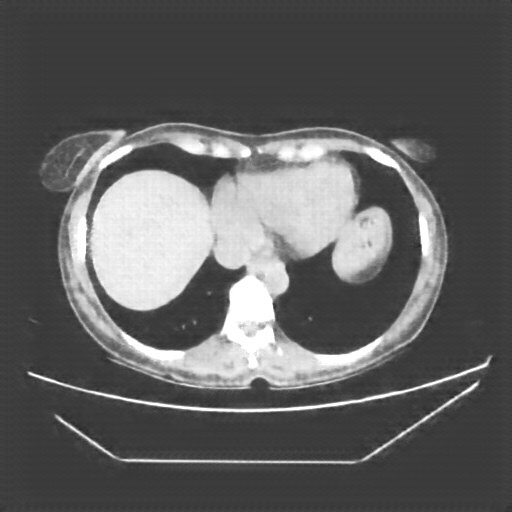

Reconstructed NATIVE CT scan (cycle consistency)

No window - Raw intensity values

Lung window (WL -600, WW 1500 β†’ Low βˆ’1350, High +150)